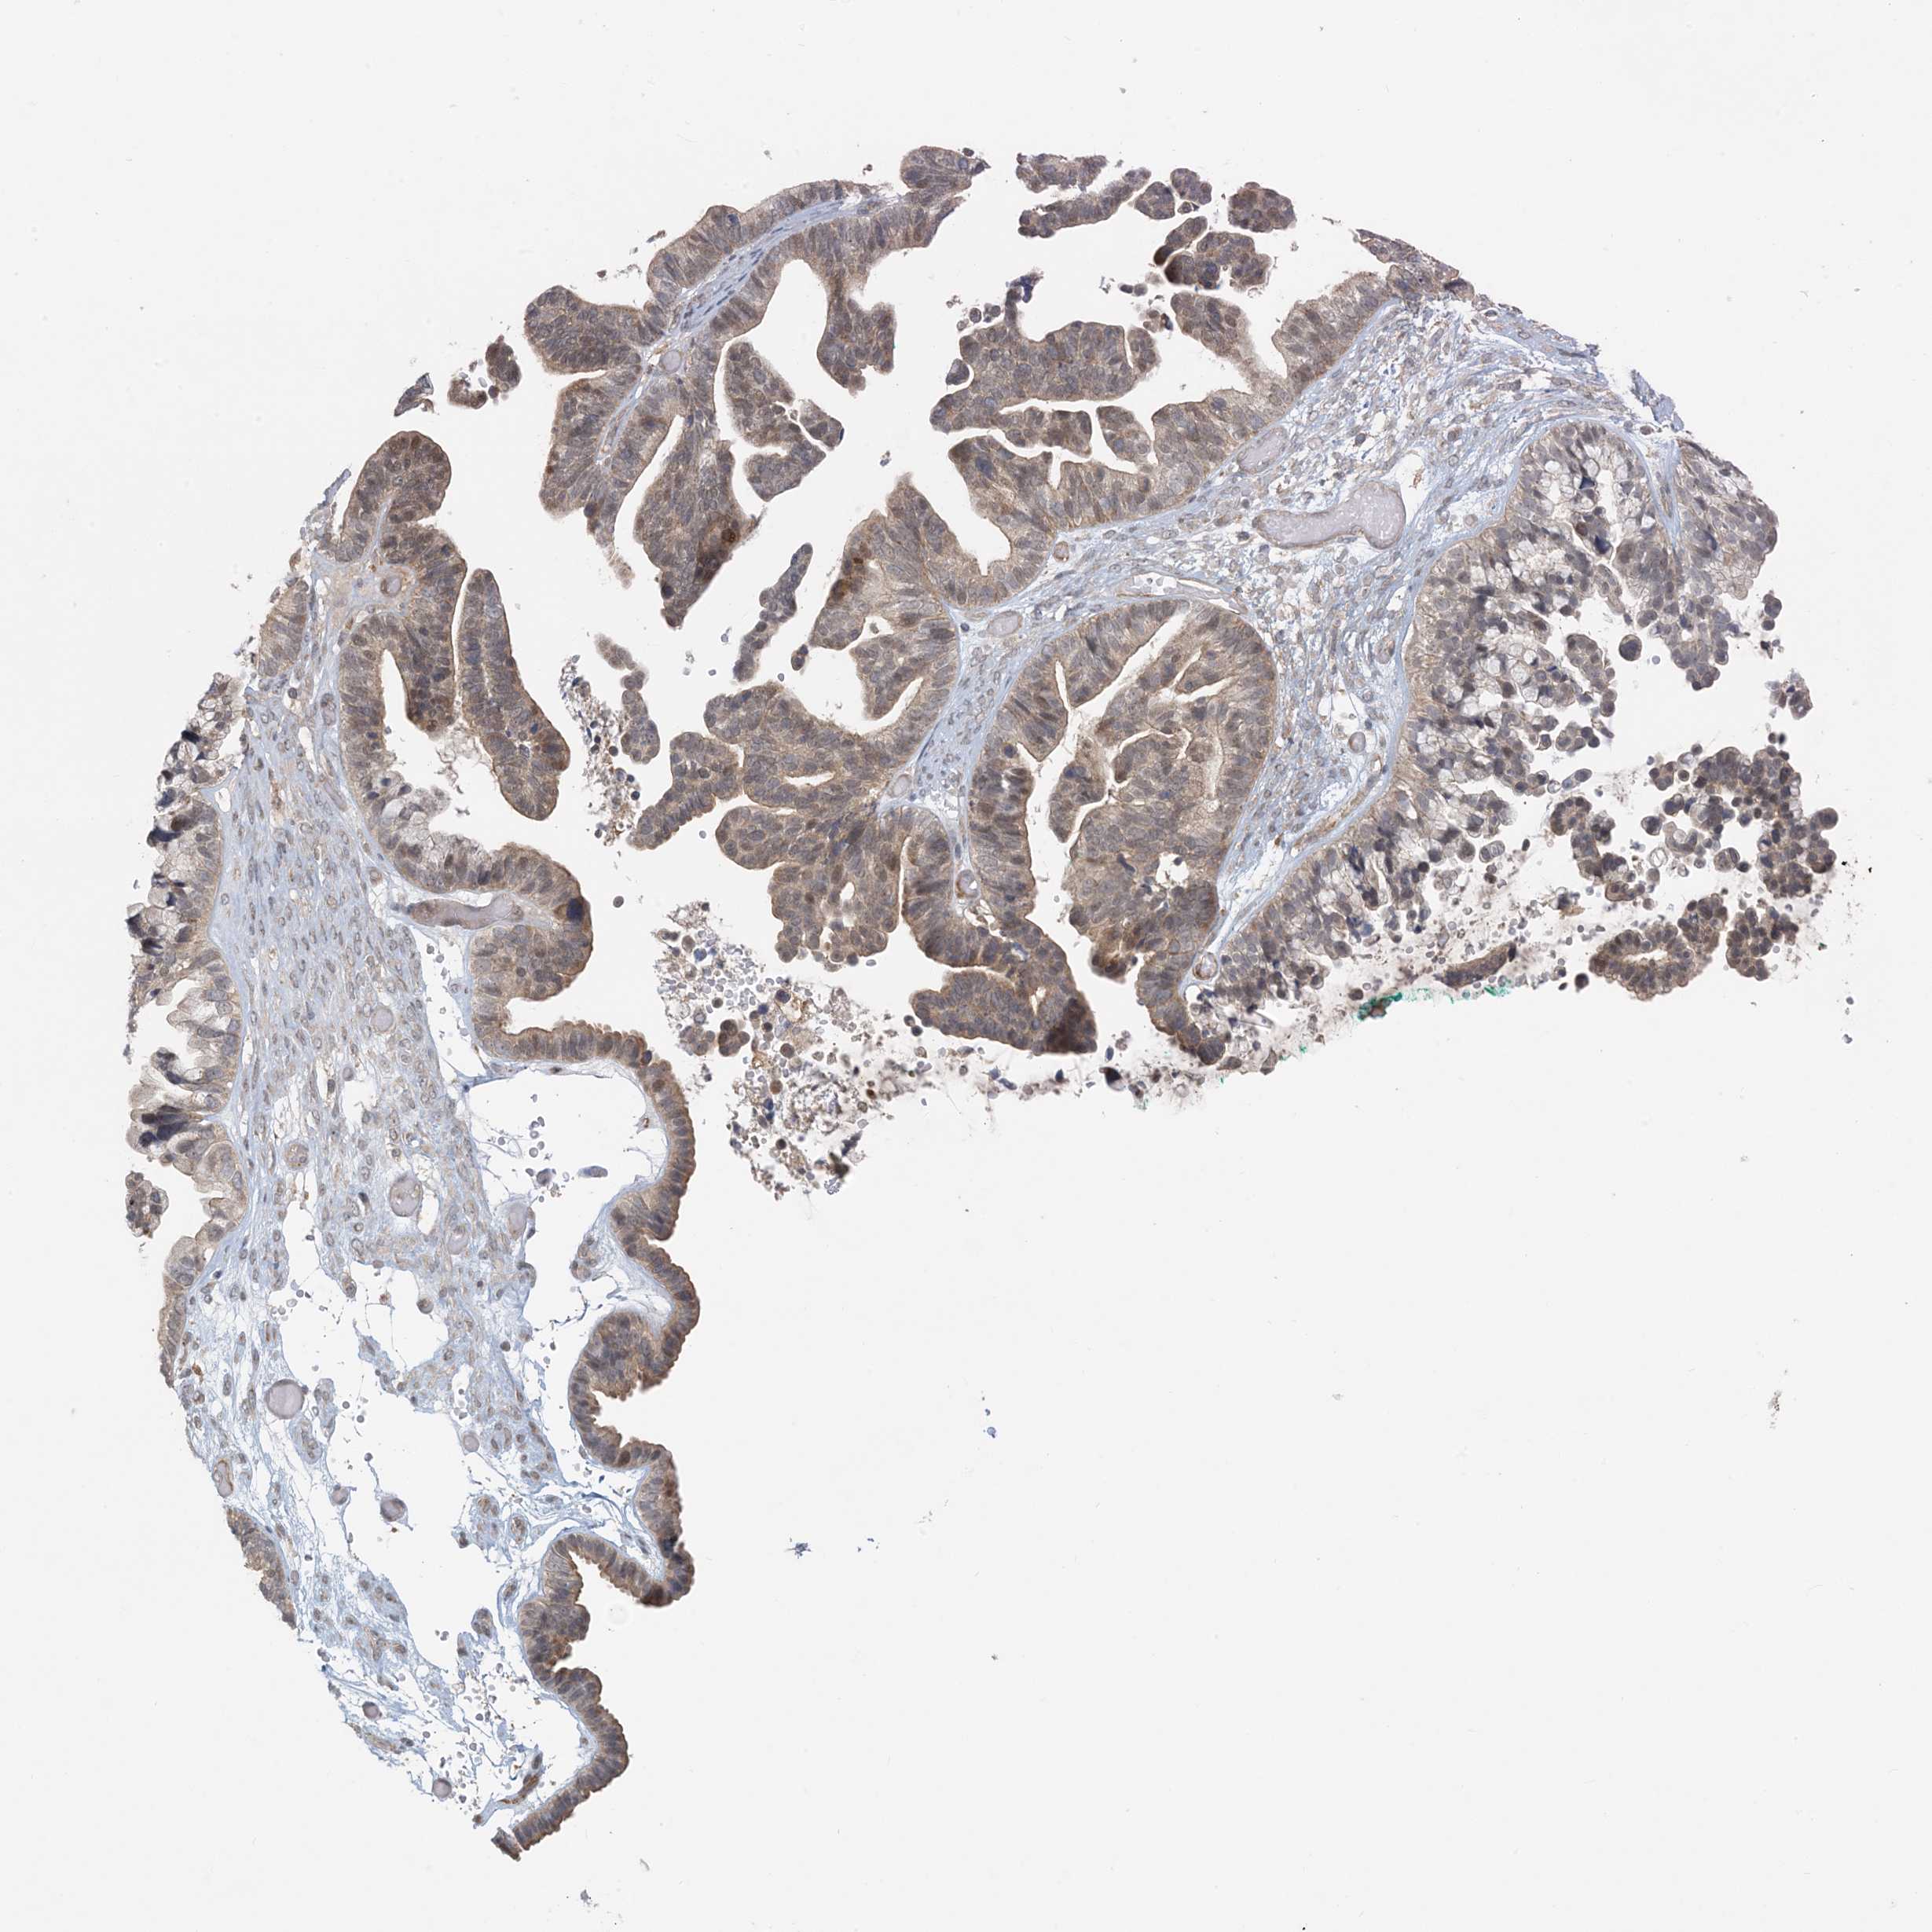

OVARIAN CANCER - Protein expressioni

A mouse-over function shows sample information and annotation data. Click on an image to view it in a full screen mode. Samples can be filtered based on level of antibody staining by selecting one or several of the following categories: high, medium, low and not detected. The assay and annotation is described here.

Note that samples used for immunohistochemistry by the Human Protein Atlas do not correspond to samples in the TCGA dataset.

Antibody stainingi

Antibody staining in the annotated cell types in the current human tissue is reported as not detected, low, medium, or high, based on conventional immunohistochemistry profiling in selected tissues. This score is based on the combination of the staining intensity and fraction of stained cells.

Each image is clickable and will lead to virtual microscopy that enables deeper exploration of all samples and also displays staining intensity scores, fraction scores and subcellular localization as well as patient and tissue information for each sample.

Antibody HPA034785

Antibody HPA034786

Staining

High

Medium

Low

Not detected

Intensity

Strong

Moderate

Weak

Negative

Quantity

>75%

75%-25%

<25%

None

Location

Nuclear

Cytoplasmic/membranous

Cytoplasmic/membranous,nuclear

Carcinoma, NOS

Cystadenocarcinoma, serous, NOS